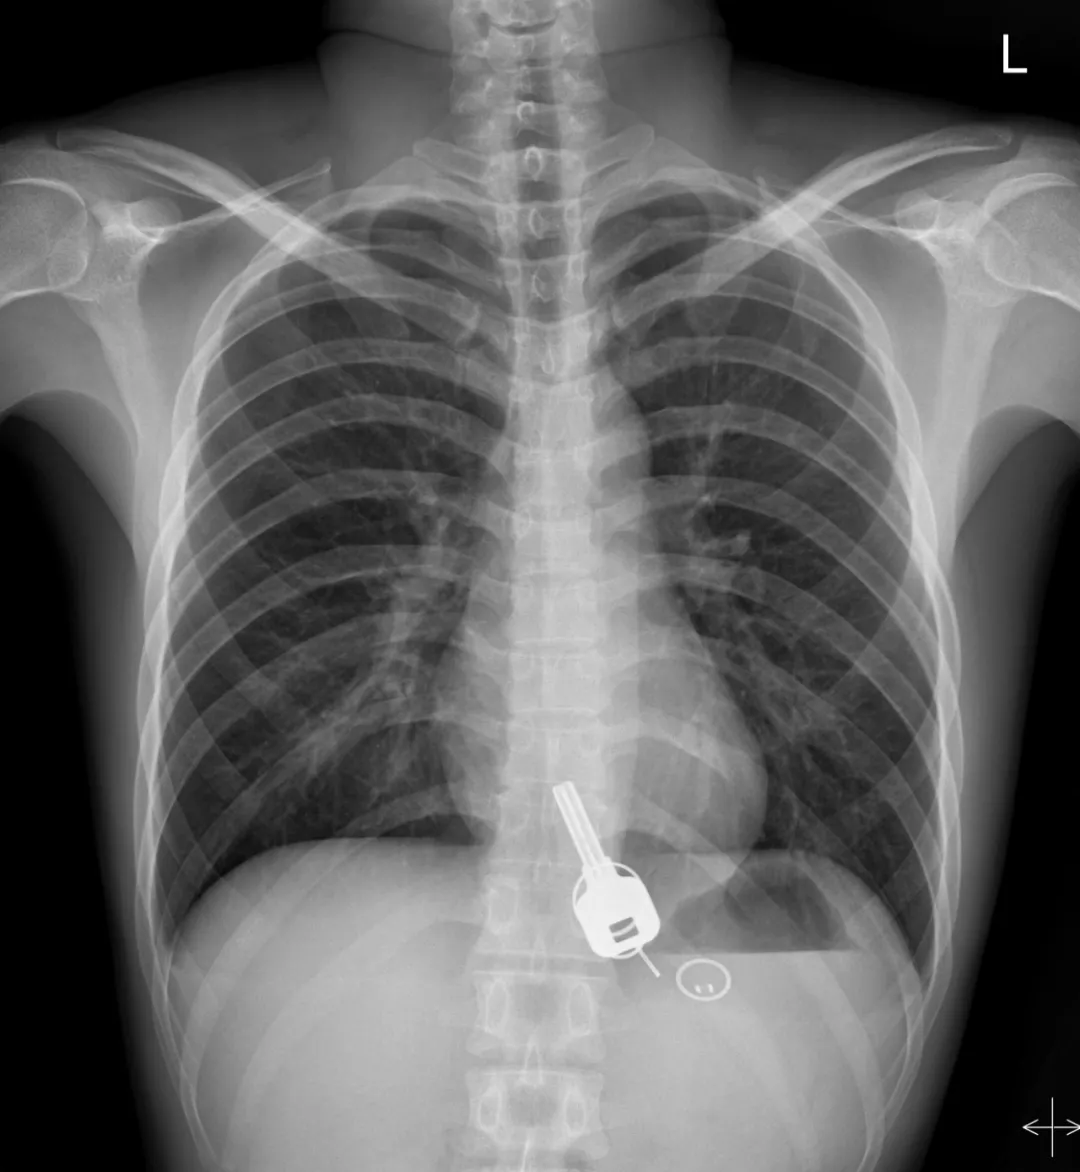

廣東東莞的常先生酒后回家找不到鑰匙,酒醒后他感到胸口疼痛,去醫(yī)院一查,發(fā)現(xiàn)一把鐵鑰匙、2個(gè)鑰匙扣、1個(gè)門(mén)禁牌清楚顯示在肚子胃區(qū)的位置上。